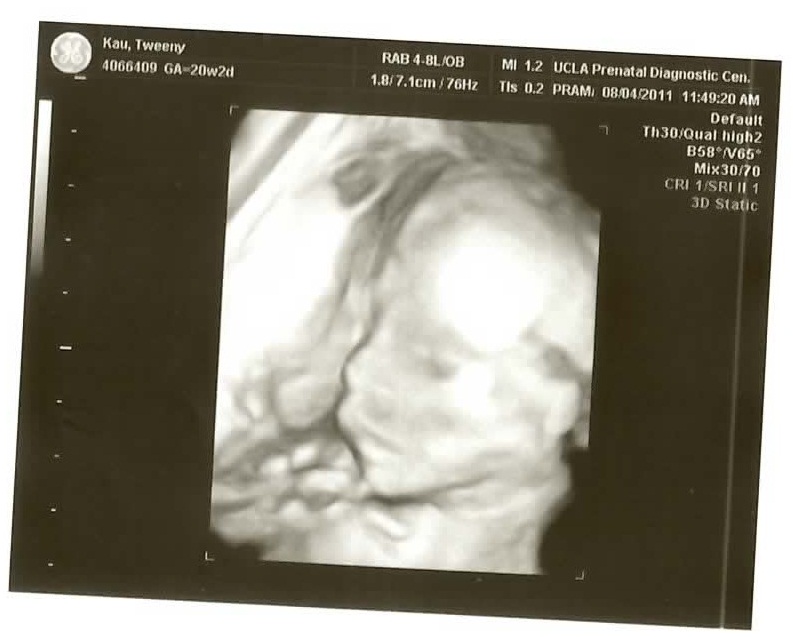

We just went back for our twenty week checkup/ultrasound and as usual they gave us a DVD which I have ripped to YouTube (it’s just everything they did.. 17:10 long.. I cut out the first 2:20 of the intern bumbling around to keep it under the 15 minute YouTube maximum).

See if you can figure out what gender it is from the ultrasound pics! Check the comments for the answer!

The 3D pictures are kind of funny because the ultrasound technicians are all like “So CUTE!” and all I can think is “for a pig face!” The one face-on isn’t so bad if you don’t look above the bottom lip I guess..